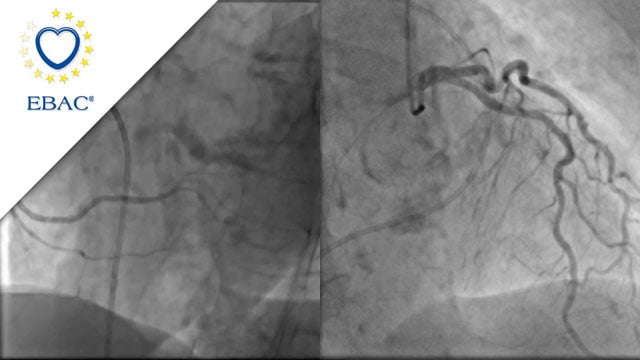

M-TEER with Mitraclip Gen5

An 83-year-old woman with HFrEF from NICM, hypertension, and persistent AF presents with worsening exertional dyspnea, severe functional MR, and moderate TR. How would you manage this patient?